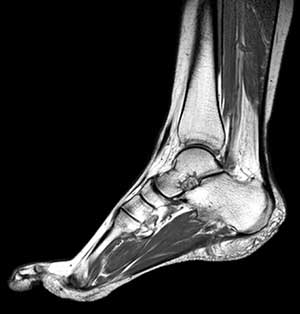

Магнитно-резонансная томография голеностопа и стопы — метод визуализации и оценки состояния костей, сухожилий, связок и сустава данной зоны. В число структур голеностопа входит большое количество разнообразных сухожилий и связок, которые вкупе с суставом отвечают за подвижность ноги, обеспечивая гибкость движений. Любого рода нарушения здесь могут серьезно повлиять на способность к передвижению.

Благодаря высокому качеству получаемых снимков с помощью МР-томографии становится возможно обнаружить патологические процессы на самых ранних стадиях и предотвратить дальнейшее развитие заболевания. МРТ голеностопного сустава может диагностировать весьма широкий спектр состояний — травмы, опухоли, артриты, инфекции. МРТ является полностью безопасным для организма, высокоточным современным видом диагностики.

МРТ помогает врачам диагностировать широкий спектр патологических состояний, которые можно увидеть на голени, уровне голеностопного сустава и стопы.